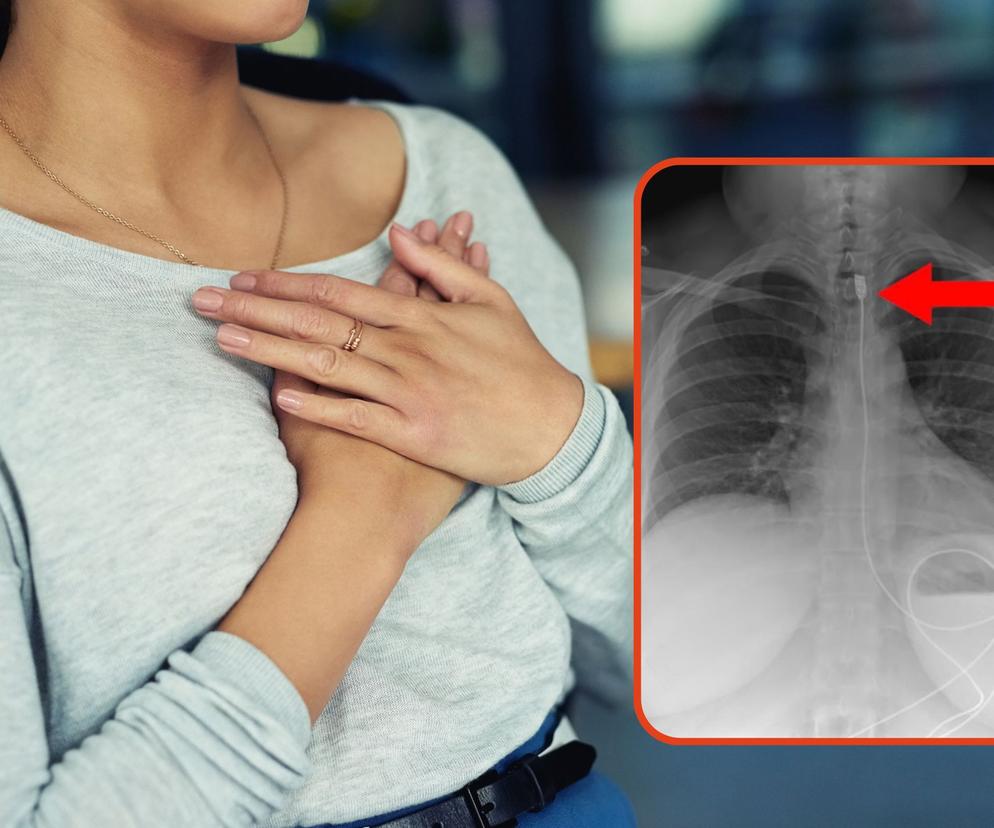

- Z czym mierzą się Zespoły Ratownictwa, a później Szpitalne Oddziały Ratunkowe? Z wieloma tematami, która dla przeciętnego obywatela wydają się po prostu niewiarygodne, niemożliwe, "ale jak do tego doszło?", "jak to możliwe?" – pytają "Gotowi Do Ratowania". Do wpisu załączyli wymowne zdjęcie RTG, na którym widać kabel zasilający do ładowarki.

Kobieta połknęła ponad metrowy przewód zasilający do smartfona. O sytuacji poinformowała Zespół Ratownictwa dopiero wtedy, gdy zaczęła odczuwać duszności spowodowane obecnością ciała obcego w górnej części przełyku.

Jak podkreślają "Gotowi Do Ratowania": "Pacjentka bez żadnych dalszych zmian chorobowych (powikłań) została wypisana ze szpitala po skutecznej i szybkiej interwencji chirurgów, którzy usunęli przewód. W takich przypadkach lekarze zakładają, że to było celowe działanie".